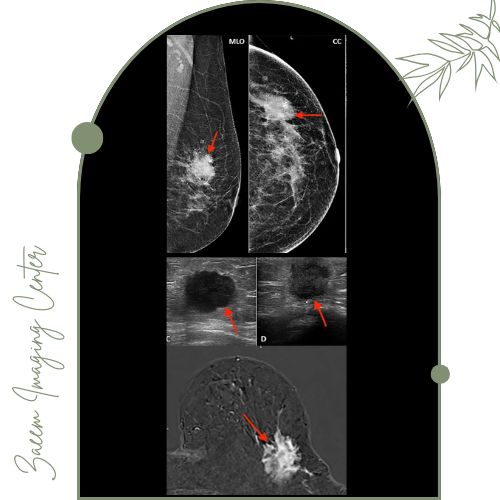

مرکز تصویربرداری پزشکی زعیم تحت مدیریت دکتر علیرضا سرزعیم (فلوشیپ مداخلهای) با همکاری دکتر سمیه زارعی و دکتر مهرناز راسته تصویربرداری تخصصی پستان را مطابق با جدیدترین استانداردهای پزشکی و پروتکلهای بینالمللی ارائه میکند. حضور پزشکان باتجربه و متخصص تضمین میکند که بررسی و تشخیص ضایعات پستان با بالاترین دقت انجام شود و گزارشهایی جامع، شفاف و قابل فهم به بیماران ارائه گردد.تجهیزات پیشرفته مرکز

در این مرکز از دستگاههای پیشرفته ماموگرافی دیجیتال و بزرگنمایی دیجیتال استفاده میشود. این تجهیزات به پزشکان امکان ثبت تصاویر با رزولوشن بالا و تشخیص دقیق تغییرات بسیار کوچک بافت پستان را میدهند.اطلاعات جمعآوری شده توسط پزشکان با تجربه با رعایت بالاترین استانداردها تحلیل و تفسیر میشود تا صحت و سرعت تشخیص تضمین گردد.

ارزیابی دقیق مشکلات پستان شامل توده، کیست، رسوبات کلسیمی و تغییرات غیرطبیعی

تفسیر نتایج توسط فلوشیپ اینترونشن و رادیولوژیستهای باتجربه